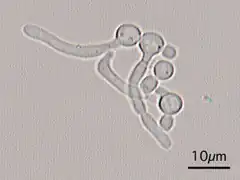

A United States study in 2022 showed that most cases of candidiasis are treated empirically (without culture, pending culture or by symptoms in cases where culture did not show candida), thus not knowing whether the subtype is Candida albicans or any other candida species.[94] For subtyping of candidiasis, a fungal culture can be performed, followed by a germ tube test in which a sample of fungal spores are suspended in animal serum and examined by microscopy for the detection of any germ tubes.[95] Colonies of white or cream color on fungal culture having a positive germ tube test is strongly indicative of Candida albicans.[95]

Germ tubes of Candida albicans